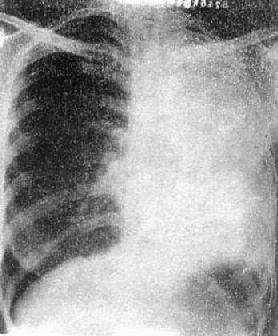

(2)肺叶不张:不同肺叶不张的X线表现不同,但其共同特点是肺叶缩小,密度均匀增高,叶间裂呈向心性移位。纵隔及肺门可有不同程度的向患部移位(图3-1-8)。邻近肺叶可出现代偿性肺气肿。

图3-1-8 各肺叶肺不张

1)右肺上叶不张:后前位表现为右肺上叶缩小呈扇形,密度增高,水平裂外侧上移。上叶轻度收缩时,水平裂呈凹面向下的弧形,明显收缩时,上叶可表现为纵隔旁三角形致密影。肺门上提,甚至上半部肺门消失。中下叶肺纹理上移而疏散,并可有代偿性肺气肿。气管可右移。

2)右肺中叶不张:较为常见,后前位表现为右肺下野内侧靠心右缘现上界清楚下界模糊的片状致密影,心右缘不能分辨(图3-1-9)。侧位上表现为自肺门向前下方倾斜的带状或尖端指向肺门的三角形致密影(图3-1-9)。上、下叶可有代偿性肺气肿。

3)左肺上叶(包括舌段)不张:左肺上叶上部较厚,下部较薄。肺不张时,后前位表现为左肺上、中肺野片状模糊影,上部密度较高,下部密度较淡,边界不清,气管左移,心左缘不清,侧位上可见整个斜裂向前移位,不张的肺叶密度高、缩小。下叶呈代偿性肺气肿,而下叶尖部向上膨胀达第2胸椎水平。

4)下叶不张:两侧肺下叶不张均表现为肺下野内侧尖端在上,基底在下的三角形致密影,肺门下移,有时肺门下部消失。上、中叶有代偿性肺气肿。右肺下叶不张较左侧显示清楚,因左侧有心影重迭,但在斜位或过度曝光片上可以显示。侧位时,下叶不张表现斜裂向后下方移位,下叶密度高。

图3-1-9 右肺中叶肺不张(正、侧位)